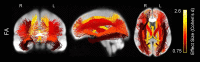

Aging is associated with widespread alterations in cerebral white matter (WM). Most prior studies of age differences in WM have used diffusion tensor imaging (DTI), but typical DTI metrics (e.g., fractional anisotropy; FA) can reflect multiple neurobiological features, making interpretation challenging. Here, we used fixel-based analysis (FBA) to investigate age-related WM differences observed using DTI in a sample of 45 older and 25 younger healthy adults. Age-related FA differences were widespread but were strongly associated with differences in multi-fiber complexity (CX), suggesting that they reflected differences in crossing fibers in addition to structural differences in individual fiber segments. FBA also revealed a frontolimbic locus of age-related effects and provided insights into distinct microstructural changes underlying them. Specifically, age differences in fiber density were prominent in fornix, bilateral anterior internal capsule, forceps minor, body of the corpus callosum, and corticospinal tract, while age differences in fiber cross section were largest in cingulum bundle and forceps minor. These results provide novel insights into specific structural differences underlying major WM differences associated with aging.